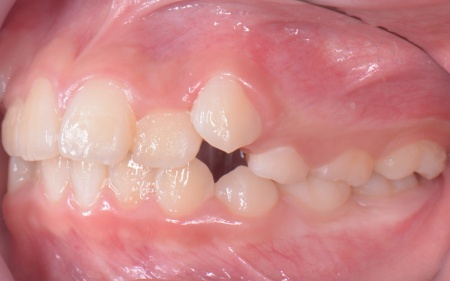

| カウンセリング | 拝見したところ、上の犬歯が歯列の外側に飛び出すように生えている、いわゆる八重歯でした。 さらに、上下の歯全体がデコボコに生えている「叢生(そうせい)」と呼ばれる状態で、これは歯が正しい位置に並ぶためのスペースが不足していることが原因だと考えられます。 このまま放置して顎の成長が完了してから矯正治療を行う場合、歯を並べるスペースを確保することが難しく、永久歯を抜く処置が必要になるケースがあります。 以上のことから、今の段階で歯並びを整える治療が必要だと診断しました。 |

患者様のご家族は「将来的な抜歯はできるだけ避けたいので、今のうちに治療をしたい」と希望されたため、成長期の段階で歯列を広げ、歯が並ぶスペースを確保する小児期の矯正治療「1期矯正」を提案しました。

メリット デメリット また、治療にあたりお口全体のバランスを確認したところ口元の突出はなく、顎のサイズはやや小さめですが、成長期であることから歯列の拡大が可能な状態だと判断しています。 以上の内容について丁寧に説明し、治療に同意いただきました。 まず、上顎に顎の骨を広げるための固定式の矯正器具「急速拡大装置」を、下顎には歯並びの幅を広げるための「リンガルアーチ」を装着します。 次に歯の位置を整えるため、ワイヤー矯正を開始します。 最後に、歯並びが整って見た目や噛み合わせにも問題がないことを確認し、装置を取り外して第1期矯正治療を終了しました。 現在も経過観察を継続していますが、歯が元の位置に戻る後戻りも見られず、残っている乳歯から永久歯への生え変わりも順調に進んでいます。 |